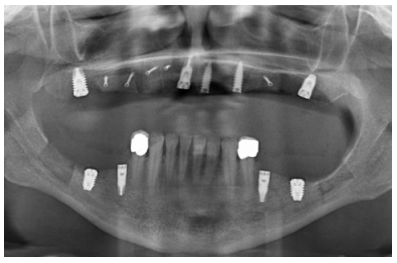

Para iniciar la fase de diagnóstico se realiza una radiografía panorámica que nos de una idea del estado general de ambos maxilares para iniciar el plan de tratamiento. En ella se ve como existe aparentemente altura en el reborde maxilar tanto a nivel anterior como posterior y un nervio dentario bajo en la mandíbula que nos permite tener una mayor cresta ósea residual disponible para la inserción de los implantes (Figura 3).